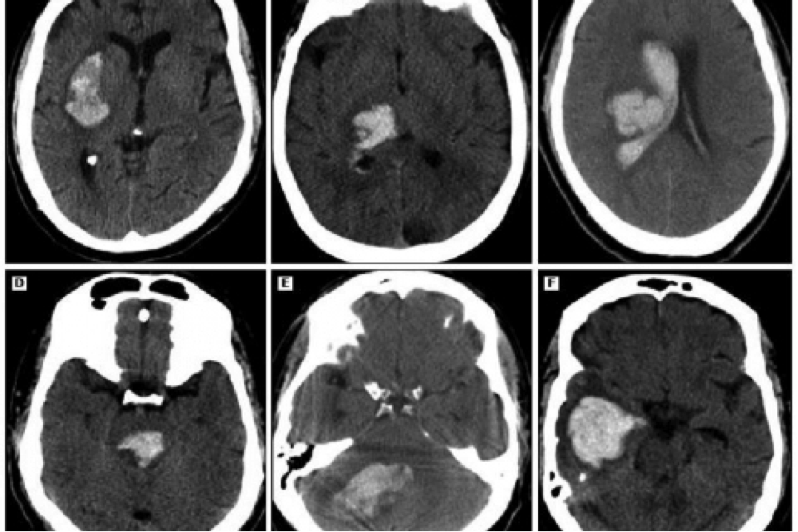

Кровоизлияние на КТ мозга (белые пятна или области с повышенной плотностью, так называемые гиперденсные). Credit: public domain

В итоге четыре признака – исходный объем гематомы, диастолическое артериальное давление, симптом «отпочковывания» (дополнительный небольшой «островок» крови рядом с основным ICH) и симптом «кляксы» (небольшая зона увеличения плотности в составе основного ICH) повышали риск увеличения гематомы.